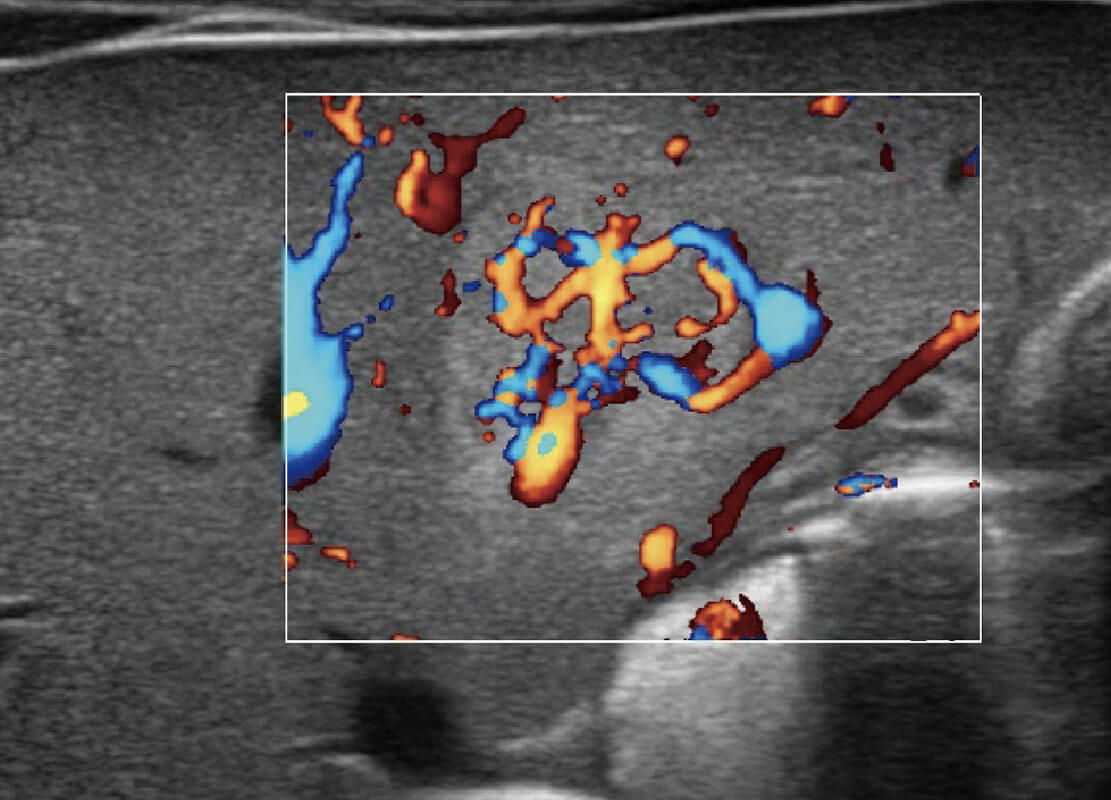

P60搭載寬頻帶線(xiàn)陣探頭、寬景成像、彈性成像技術(shù),為您提供乳腺應(yīng)用方案。P60支持高頻相控陣探頭、線(xiàn)陣探頭、腹部高頻探頭、腹部微凸探頭等,豐富的探頭群搭載敏感的彩色血流成像,適用于新生兒多種臟器檢測(cè)要求,滿(mǎn)足新生兒篩查需求。

乳腺癌顯微血流

新生兒肝血管癌